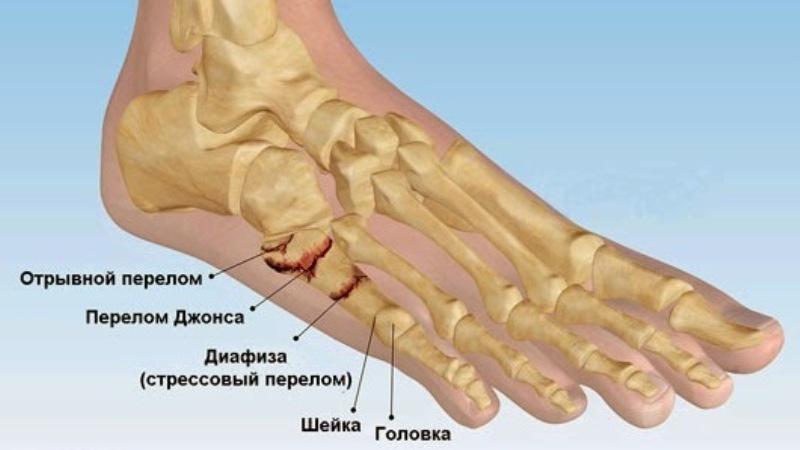

Перелом плюсневой кости обычно происходит из-за падения тяжелого предмета на стопу или ее защемления. При таком повреждении различают переломы головки, шейки или тела кости. Особенно часто встречается перелом Джонса (травма пятой плюсневой кости), который возникает при повороте стопы наружу.

На фото ниже вы можете увидеть перелом костей стопы: